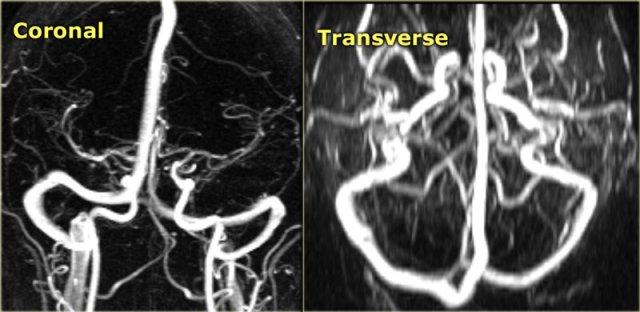

MR-venography

The MR-techniques that are used for the diagnosis of cerebral venous thrombosis are:

Time-of-flight (TOF), phase-contrast angiography (PCA) and contrast-enhanced MR-venography:

-

Time-of-Flight angiography is based on the phenomenon of flow-related enhancement of spins entering into an imaging slice.

As a result of being unsaturated, these spins give more signal that surrounding saturated spins. - Phase-contrast angiography uses the principle that spins in blood that is moving in the same direction as a magnetic field gradient develop a phase shift that is proportional to the velocity of the spins.

This information can be used to determine the velocity of the spins. This image can be subtracted from the image, that is acquired without the velocity encoding gradients, to obtain an angiogram. - Contrast-enhanced MR-venography uses the T1-shortening of Gadolinium.

It is similar to contrast-enhanced CT-venography.

When you use MIP-projections, always look at the source images.

On the left a lateral and oblique MIP image from a normal contrast-enhanced MR venography.

Notice the prominent vein of Trolard (red arrow) and vein of Labbe (blue arrow).

Every MR techniques has its own pitfalls as we will discuss in a moment.

Contrast-enhanced MR venography has the disadvantage that you need to give contrast, but has less pitfalls.